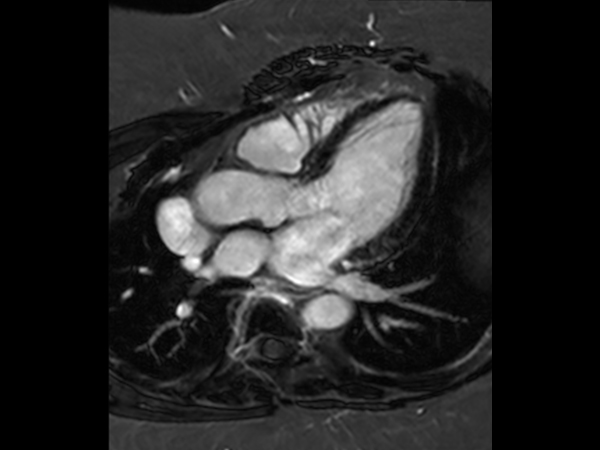

Obese patient, BMI 52, referred for cardiac MR imaging

bTFE, 4 chamber view